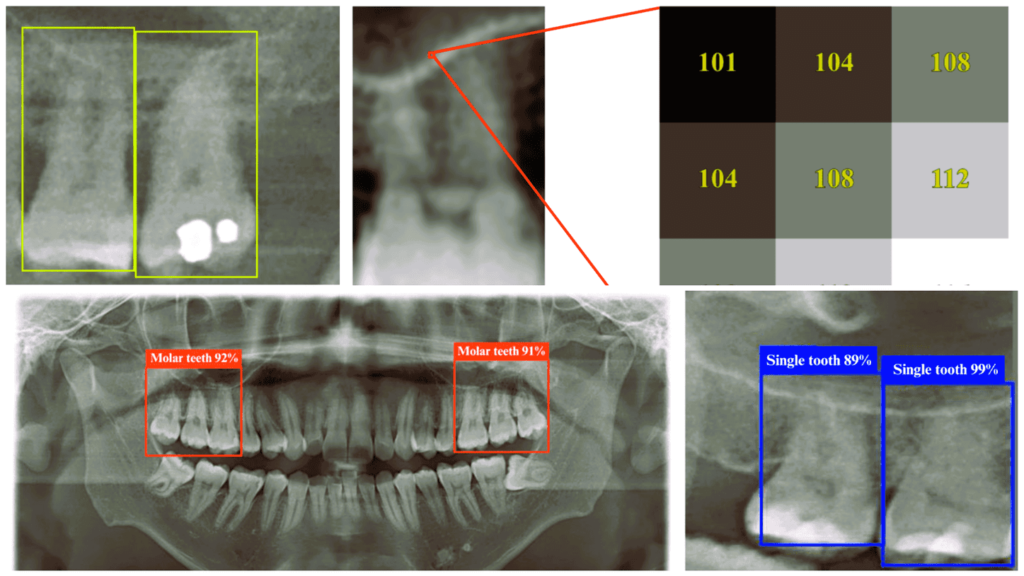

By training deep learning models on dental panoramic radiograph (DPR) images, the researchers found a way to detect key anatomical relationships—such as the proximity of tooth roots to sinuses—with unprecedented accuracy. The study used the YOLO 11n deep learning model, achieving an impressive 98.2% accuracy, outperforming traditional detection methods.

YOLO (You Only Look Once) is a state-of-the-art object detection algorithm known for its speed and accuracy. The YOLO 11n model, an improved version, is optimized for medical imaging tasks, enabling it to identify teeth and sinus structures with high precision in a single pass through the image. Unlike conventional diagnostic methods, which require multiple steps and expert interpretation, YOLO 11n rapidly pinpoints the affected areas in real time, making it an invaluable tool for dental professionals.

Image above shows sample dental X-rays or DPRs as seen by the YOLO 11n deep learning model, which is able to identify tooth structures with up to 98.2% accuracy (Photo by Pei-Yi Wu et al, 2025)